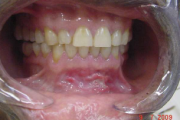

Suu limaskesta haavandid

- Alati tuleb kontrollida hambaproteese. – Haavandi põhjuseks võib olla odontoloogiline infektsioon. – Igal juhul tuleb arvestada vähi võimalusega. Reeglina tuleb võtta biopsia haavanditest, mis kahe nädala jooksul ei parane. – Konsulteerida hambaarstiga; patsiendid, kellele tuleb teha Loe edasi »